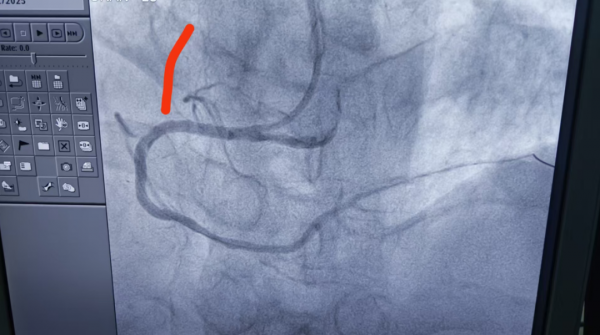

3、69歲男性,雙支病變,行介入治療。